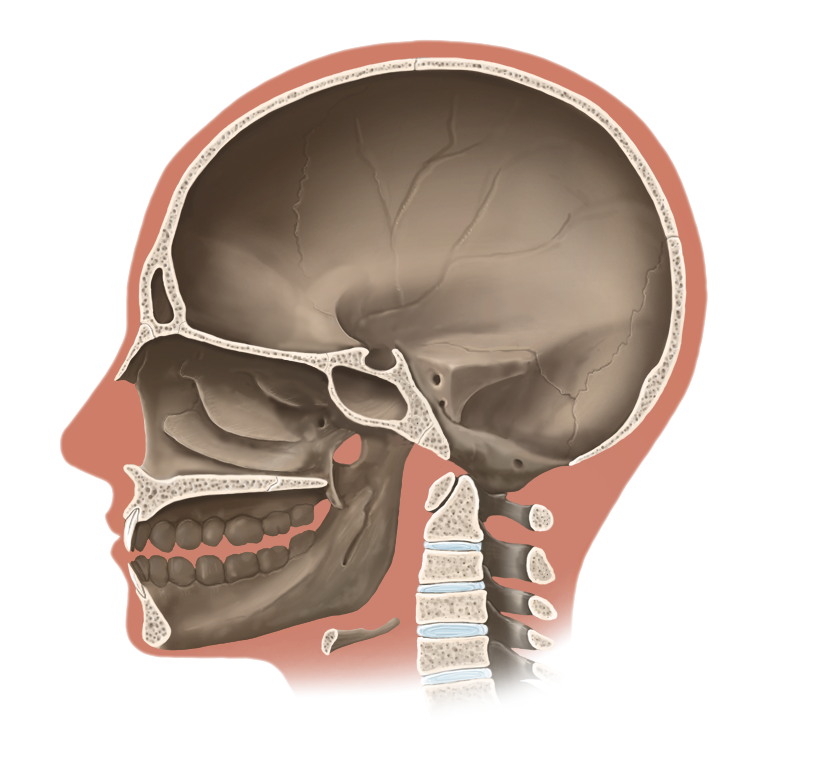

Medical Illustration

All images are works made for hire and are the exclusive property of the client. These are shown as sample purposes of my work only. For licensable work, please see my Illustration Services page.

Medical Illustrator for Precision Graphics, Lachina, and Human Kinetics Publishing (current)

Contract freelancer for many others, some examples of my work below.